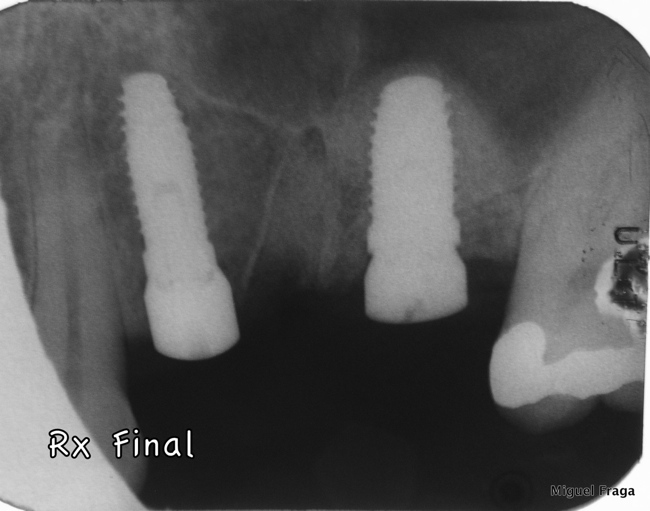

Paciente, com ausência dentes 24 e 26, e com 25 indicado para extração. Colocaram-se implantes no local do 24 e 26. Neste último, a altura óssea era de 3 mm, e por isso o protocolo, consistiu na preparação com broca aquém da cortical do seio maxilar. Seguidamente utilizaram-se osteótomos, com os quais provocamos a fractura da cortical e a elevamos. A membrana de Schneider foi elevada e o seio maxilar foi preenchido através do leito implantar. Para executar este tipo de procedimentos utilizamos Osteotomos e “magnetic mallet”. No essencial esta técnica é baseada no protocolo de Summers, e, entre outros, no livro “The Percrestal Sinuslift” de Georg Watzek.

Neste caso com reduzida altura óssea foi possível num mesmo tempo cirúrgico colocar implantes, elevar o seio e ser minimamente invasivo. Ao fim 5 meses o caso estava reabilitado proteticamente.